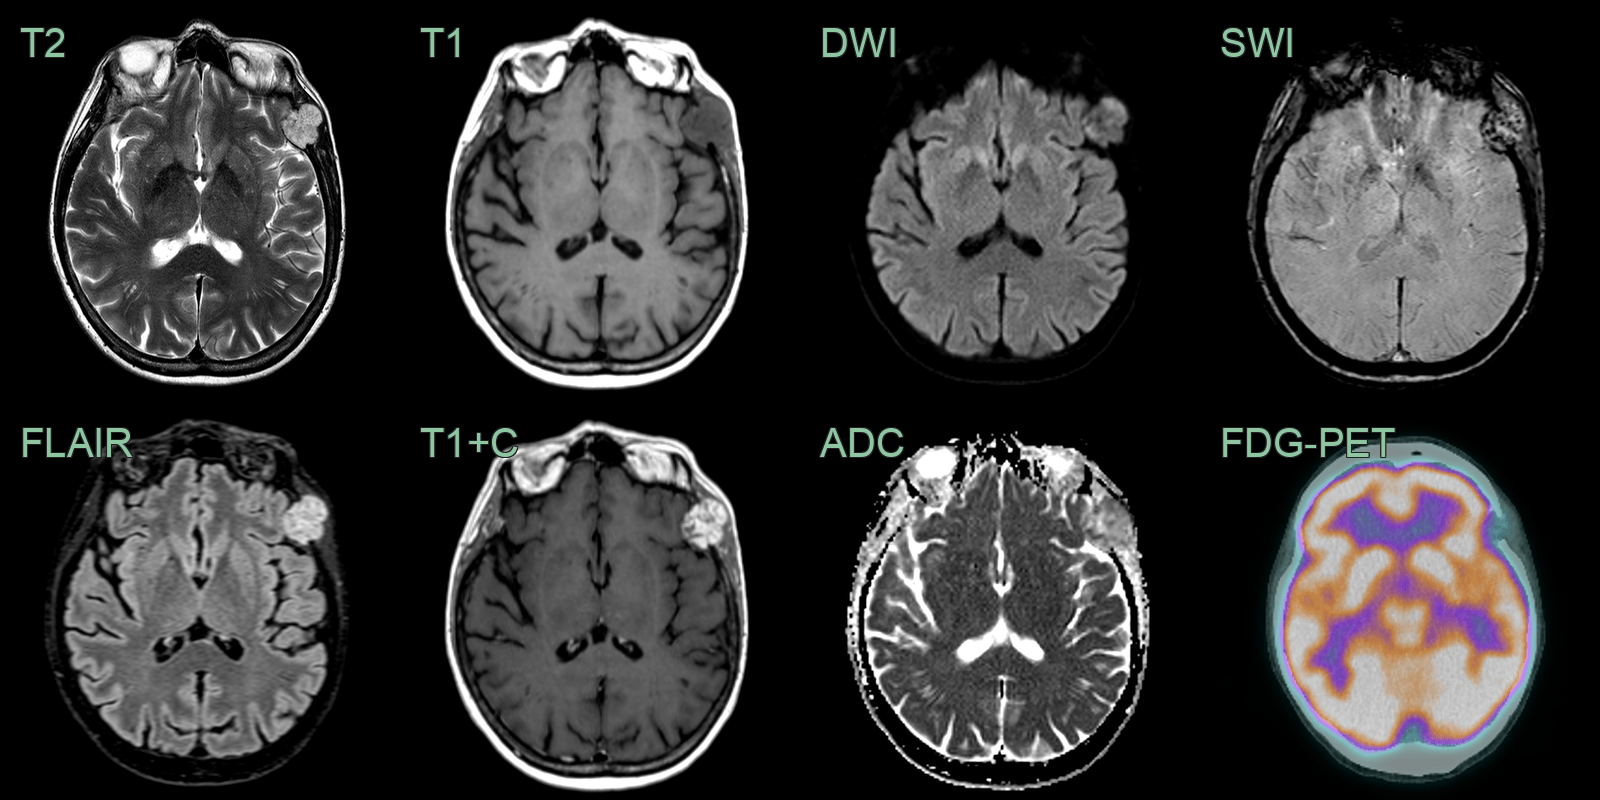

• An incidental lesion in the intradiploic space of the parietal bone contained fat and did not enhance (allowing for prominent nearby veins).

• The bone appearance was not typical, but a radiological diagnosis of a fatty hemangioma was given. A lipomatous lesion is also possible.